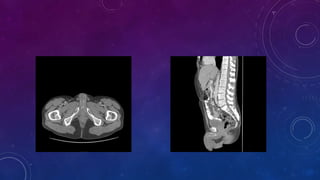

• Failed kidney transplant

• Seminal vesicle / vas deferens calcification

• #62 Failed kidney transplant Seminal vesicle / vas deferens calcification